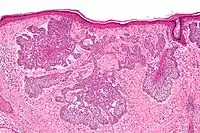

Nodular basal-cell carcinoma (also known as "classic basal-cell carcinoma") accounts for 50% of all BCC.[25] It most commonly occurs on the sun-exposed areas of the head and neck.[26]: 748 [27]: 646 Histopathology shows aggregates of basaloid cells with well-defined borders, showing a peripheral palisading of cells and one or more typical clefts.[25] Such clefts are caused by shrinkage of mucin during tissue fixation and staining.[28] Central necrosis with eosinophilic, granular features may be also present, as well as mucin. The heavy aggregates of mucin determine a cystic structure. Calcification may be also present, especially in long-standing lesions.[25] Mitotic activity is usually not so evident, but a high mitotic rate may be present in more aggressive lesions.[25] Adenoidal BCC can be classified as a variant of NBCC, characterized by basaloid cells with a reticulated configuration extending into the dermis.[25]

Cleft.